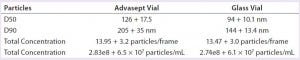

Table 3: Nanoparticle tracking data analysis (MAb formulation)

NTA Analysis: As Table 3 shows, we observed slightly larger aggregates in the Advasept vials than in glass. However, the total number of particles are statistically comparable for both container–closure systems (Figures 5–7).